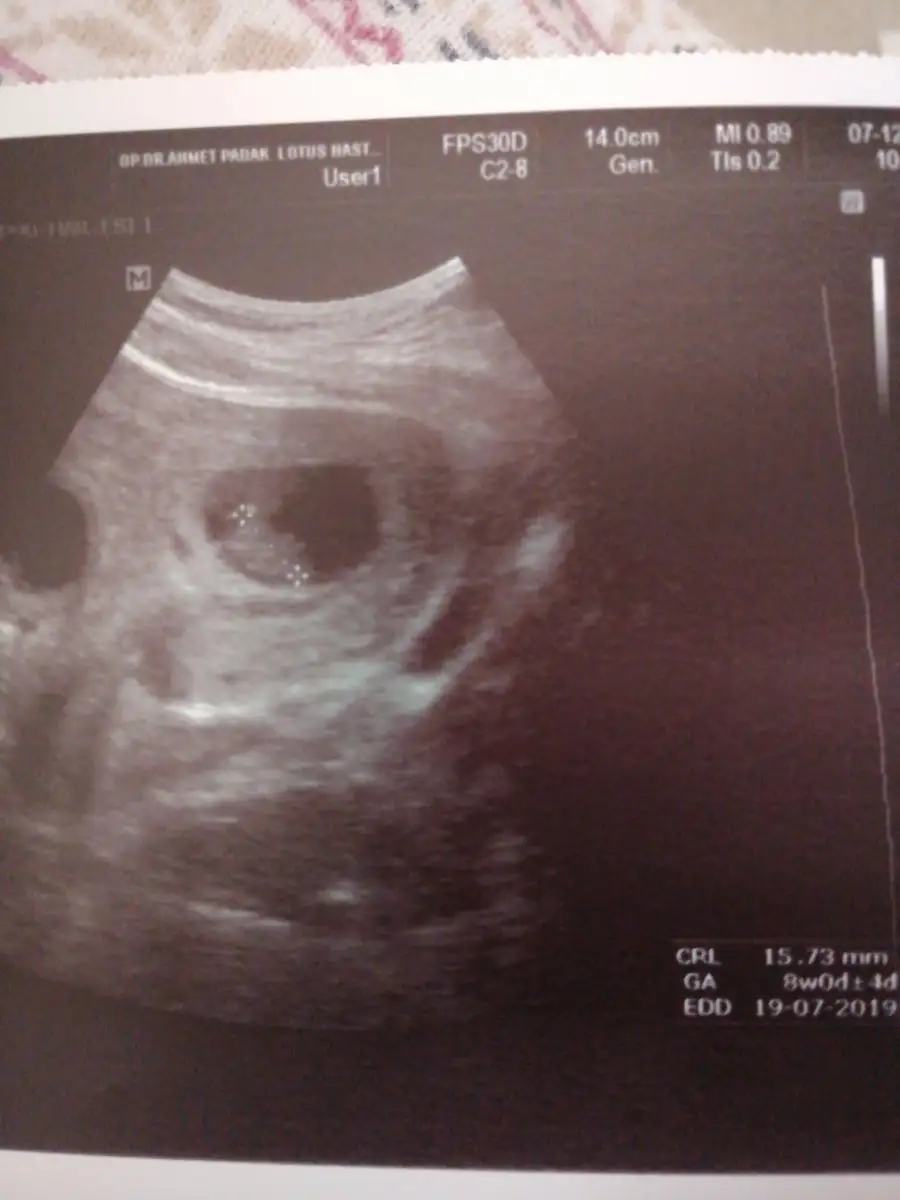

gayet iyi bence boyu. 7w+6g benim 14,6mm yazıyorSenin bebegin boyu kaçtı canım. Benim en son 15.73mm di

Ben enson 26 kasımda gittim canım ozaman 1cm’e yakın demişti bu çarsamba kontrolüm var, ozaman sana net söyleyeyim.Senin bebegin boyu kaçtı canım. Benim en son 15.73mm di

İnşallah iyidirgayet iyi bence boyu. 7w+6g benim 14,6mm yazıyor